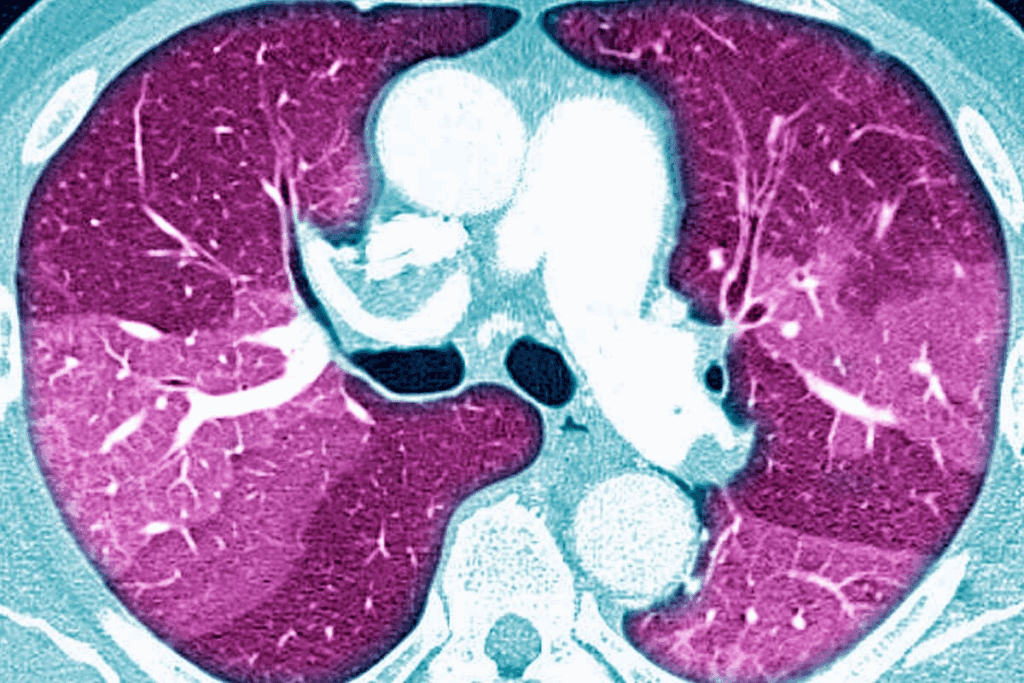

A CT scan lung biopsy takes small tissue samples from lung areas that look off. We use live CT scans to guide the needles. This makes sure we get the right tissue for a better diagnosis.

A CT-guided lung biopsy is a precise way to get tissue samples from the lungs. It helps diagnose lung conditions. The procedure uses CT imaging to guide a needle into the lung tissue or nodule for accurate sampling.

CT guidance makes the biopsy more accurate. It provides real-time images. This lets the doctor precisely locate and guide the needle, increasing the chance of getting a good tissue sample.

CT guidance is key to improving lung biopsy accuracy. It offers real-time imaging. This helps doctors navigate the needle through lung tissue with high precision, reducing sampling errors.

During the procedure, CT imaging shows live pictures of the lung. It guides the needle to the abnormal area with great precision. This real-time imaging is vital for the biopsy’s success, allowing for quick adjustments.

CT imaging uses X-rays to create detailed images of the body. In a CT scan guided needle biopsy, these images guide the needle to the lung nodule or abnormality.

The CT scanner takes images from different angles. These are then combined into a 3D image. This helps the radiologist locate the abnormality and plan the biopsy.